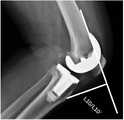

FIG. 3 is a second schematic diagram of a knee joint line using the deep learning-based pre-revision surgery planning method after total knee replacement provided by the present invention;

2. The change of the joint line before and after the revision surgery was measured with the tibial adductor muscle stop as a reference point.

As shown in FIG. 3, on the X-ray orthodontics of the knee joint, 1 perpendicular line is drawn from the inflection point of the cortical bone of the metaphyseal segment of the medial condyle (the adductor tubercle of the femur) to the line connecting the farthest end (i.e., the lowest point) of the articular surface of the medial condyle and the farthest end (i.e., the lowest point) of the articular surface of the lateral condyle. The vertical line segment is the joint line, and the length of the vertical line segment is the length of the joint line. The anterior and posterior joint line lengths for revision are designated L4 and L4', respectively. The length of the joint line is L4-L4'. In fig. 3, L4 and L4' are used as examples only, and do not mean that the joint line before and after revision must be the same.